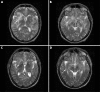

Cerebral vasculitis as a primary manifestation of systemic lupus erythematosus